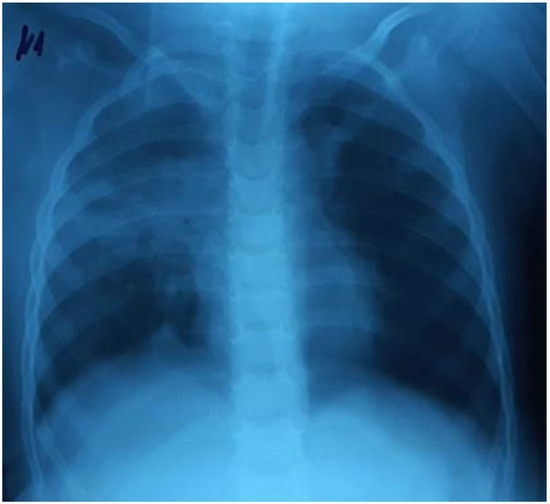

Clinical Characteristics and Quality of Life of Persistent Symptoms of COVID-19 Syndrome in Indonesia

by Agus Dwi Susanto, Fathiyah Isbaniah, Irandi Putra Pratomo, Budhi Antariksa, Erlang Samoedro, Muhammad Taufik, Fadlika Harinda and Fariz Nurwidya

Introduction: Coronavirus disease-2019 (COVID-19), caused by the severe acute respiratory syndrome coronavirus-2 (SARS-CoV-2) manifests in a broad clinical spectrum. COVID-19 survivors report various symptoms up to several months after being infected. The purpose of this study was to determine the prevalence of persistent COVID-19 syndrome in Indonesia, the factors that influence the incidence, and the quality of life. Methods: This was a cross-sectional study with an online questionnaire conducted in January 2021. Inclusion criteria were: adult Indonesian citizens who had recovered from COVID-19, and were confirmed negative by RT-PCR of nasal swabs or had undergone an isolation period for a minimum of 14 days. Data analysis was performed by the Chi-square test, followed by multivariate analysis with the backward likelihood ratio method. Results: From a total of 385 respondents, 256 (66.5%) experienced persistent COVID-19 syndrome. The most prevalent symptoms were fatigue (29.4%), cough (15.5%), and muscle pain (11.2%). Of the five aspects of quality of life, the most commonly reported aspects were pain/discomfort and anxiety/depression. The risk of persistent COVID-19 syndrome was significantly higher in subjects with older age, comorbidities, higher clinical severity, previous treatment in hospital, presence of pneumonia, and those who had required oxygen therapy. In the multivariate analysis, the most influential factor for the incidence of persistent COVID-19 syndrome was pneumonia (aOR 2.31, 95% CI 1.29–4.11, p < 0.002). Conclusions: The prevalence of the persistent COVID-19 syndrome in Indonesia was high, which affects the quality of life of COVID-19 survivors. Pneumonia was the main factor that influenced the incidence of persistent COVID-19 syndrome. Further research with a larger sample size and a longer study time is recommended to control COVID-19 and its impact on the health and quality of life of COVID-19 survivors. Full article

Show Figures